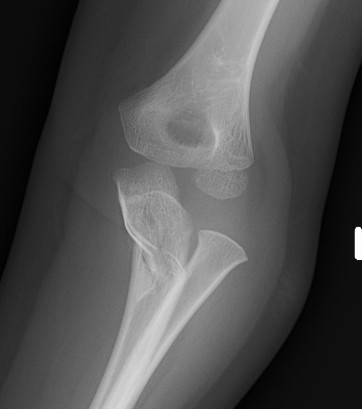

Case 1. Missed Monteggia, injury 6 months ago